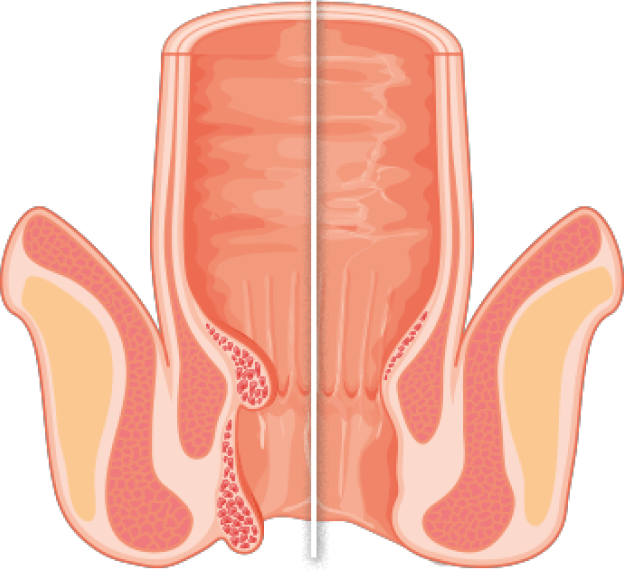

W JAKI SPOSÓB BLOOD CONTROL PRO MAX ULTRA ELIMINUJE HEMOROIDY?

Hemoroidy

Zdrowy odbyt

Niewiarygodnie skuteczne działanie Blood Control PRO MAX ULTRA zawdzięcza swojemu naturalnemu składowi oraz specjalnej technologii produkcji. Zawiera ponad 25. naturalnych składników.

Naturalne substancje wchodzące w skład Blood Control PRO MAX ULTRA już po 1. zastosowaniu niwelują objawy żylaków odbytu.

- W 100% naturalne składniki eliminują ból, pieczenie i świąd

- Naczynia krwionośne 5-krotnie mocniej obkurczają się, krwawienie ustępuje

- Zmniejsza się przepuszczalność żył, stają się one w 130% bardziej elastyczne

- Następuje eliminacja skrzepów powstałych w naczyniach krwionośnych, a wypróżnianie w końcu jest proste

HEMOROIDY

Hemoroidy wewnętrzne

Żyły

Żyły

Hemoroid zewnętrzne

Kanał odbytu

ZDROWA ODBYTNICA

Ścianka mieśniowa

Mięsień zwieracza zewnętrznego

Błona śluzowa

Mięsień zwieracza wewnętrznego

Kanał odbytu

Skóra